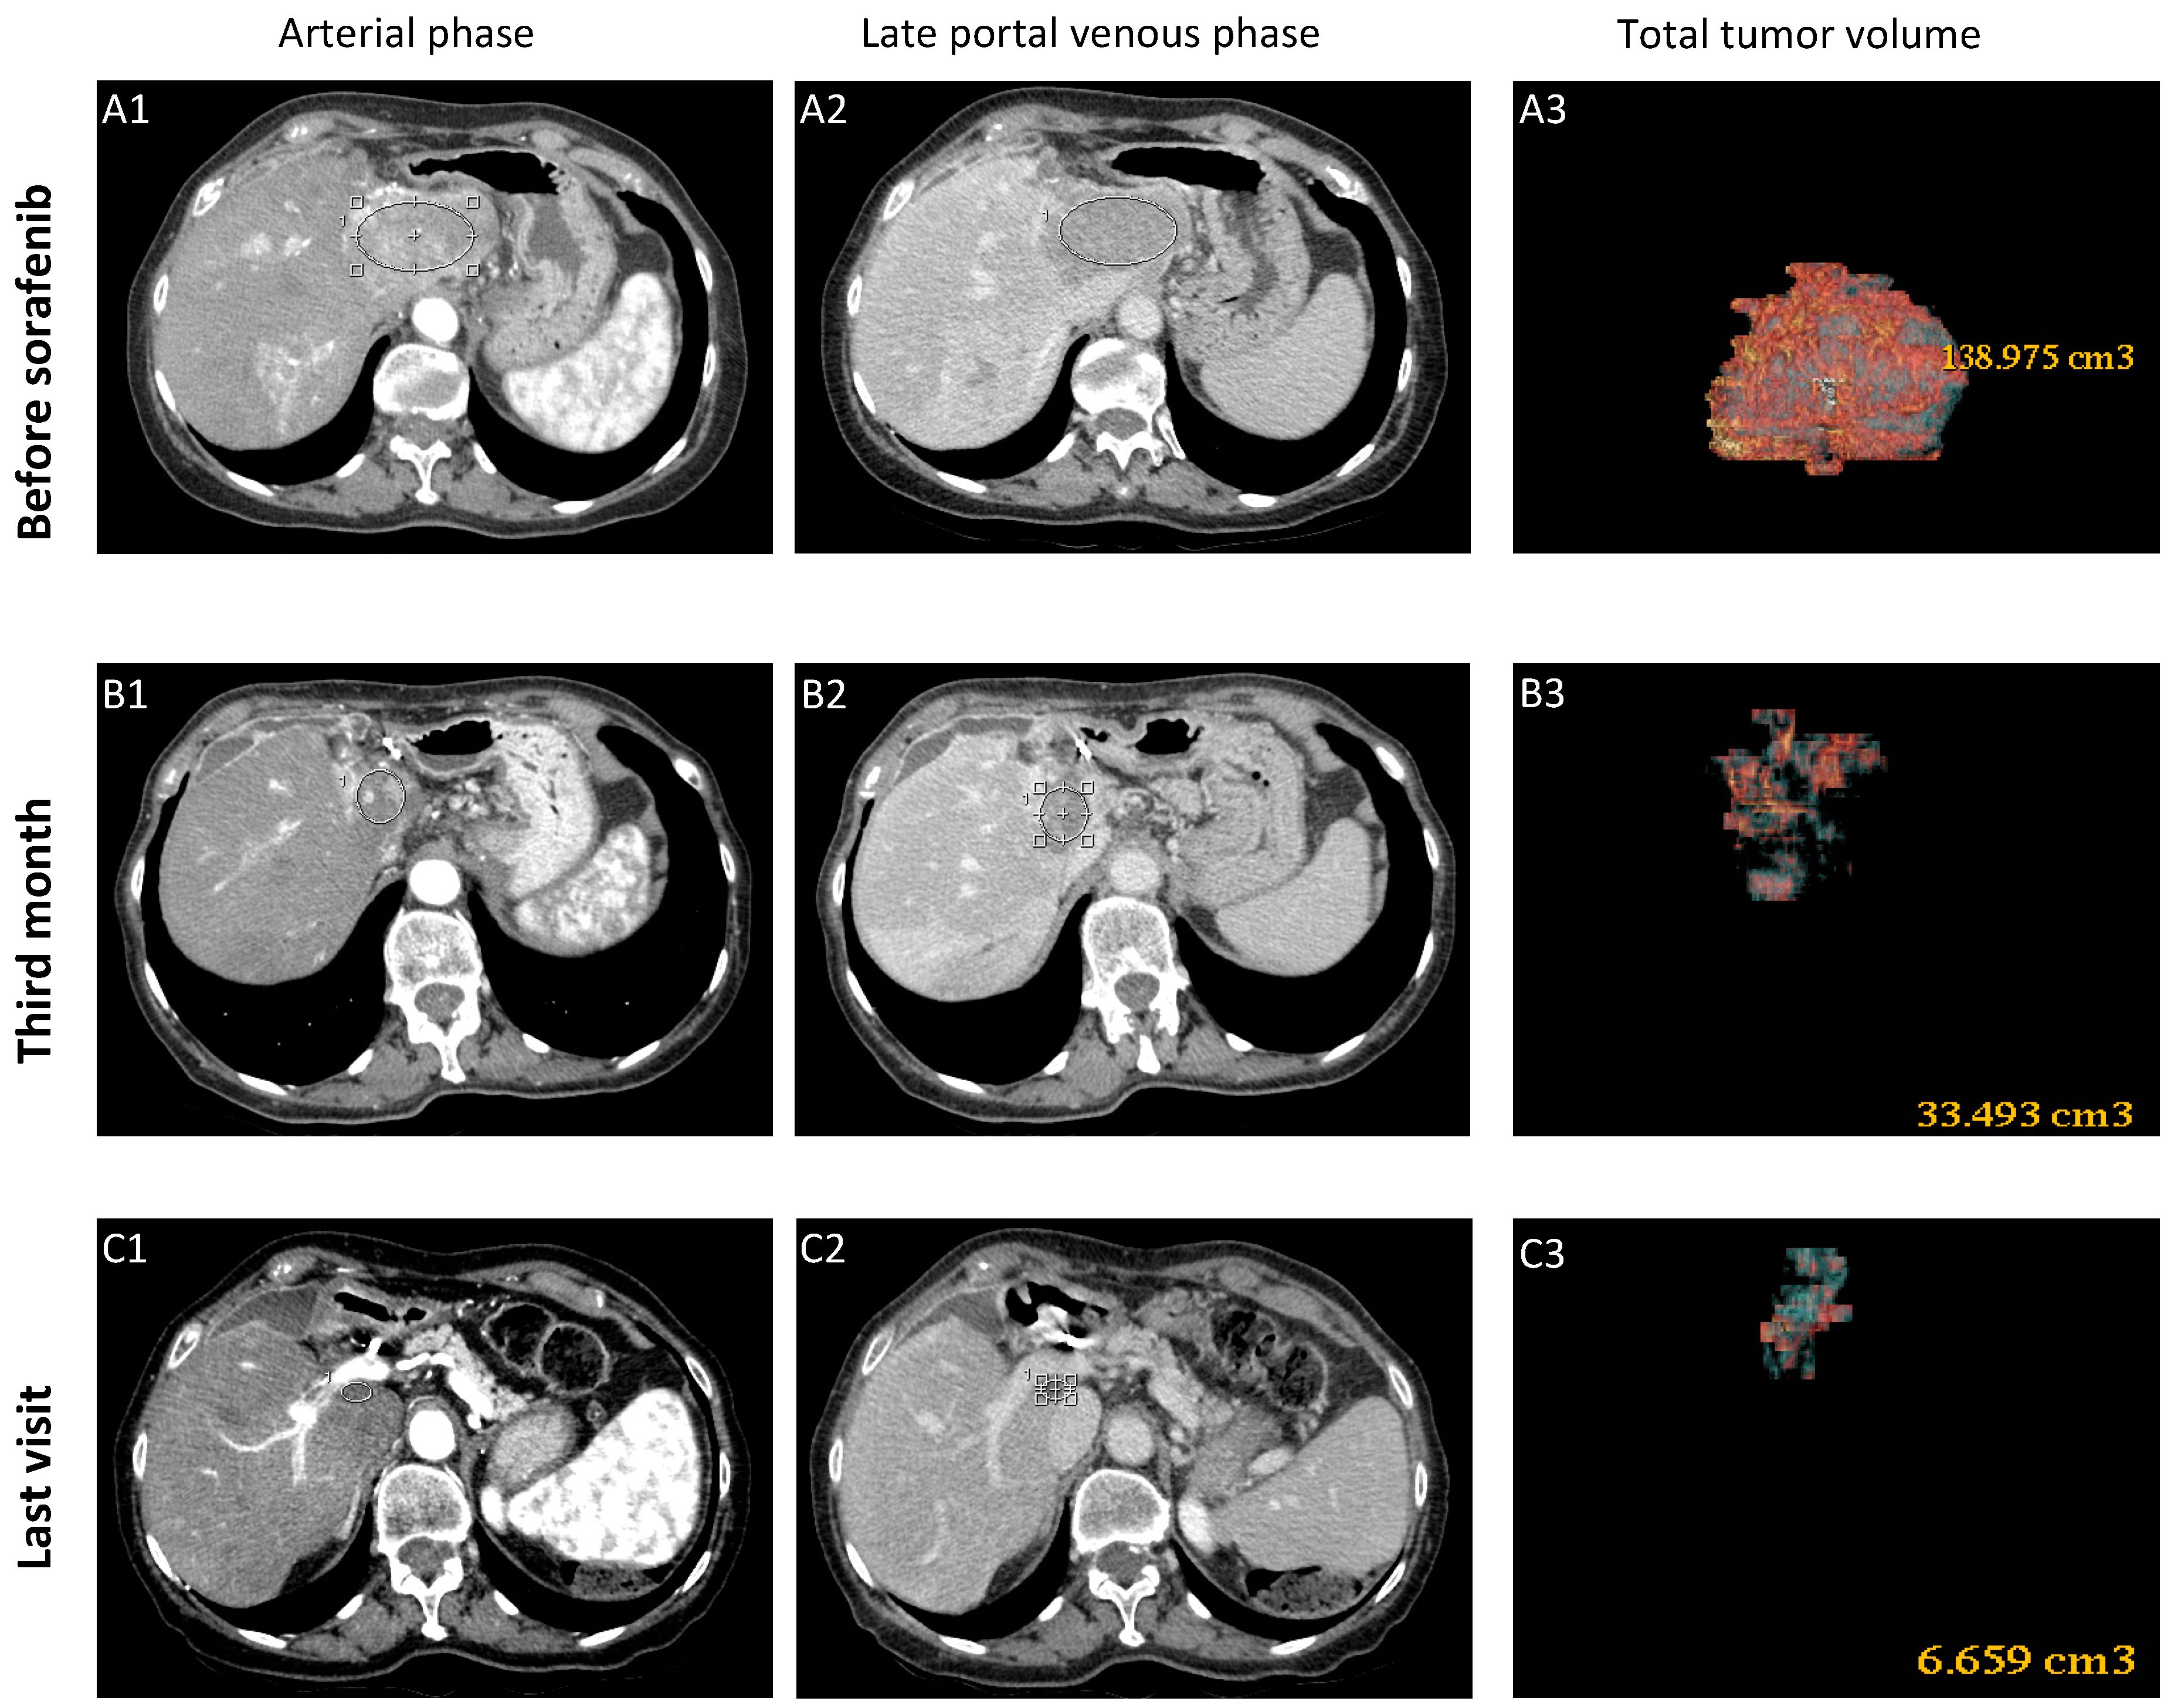

3.1.1. Case-1 (CR to Sorafenib)